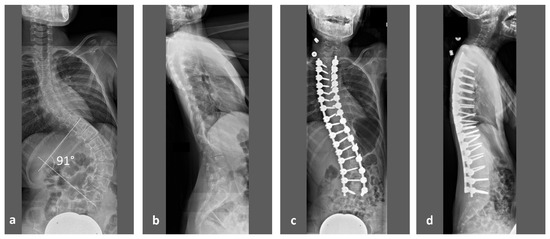

While early deformity during childhood is mainly treated by conservative bracing, advanced scoliosis will need surgical spinal deformity correction (Figure 1). In our clinic, preoperative computed tomography (CT) of the spine in sedation will be performed for deformity analysis, presurgical planning and intraoperative navigation. The same datasets also allow vertebral vBMD measurements through asynchronous calibrated quantitative computed tomography (QCT). Such measurements overcome inherent limitations of Dual-energy X-ray absorptiometry (DXA) when examining patients with disability. Stable positioning and severe scoliosis have been described by the International Society for Clinical Densitometry (ISCD) in its official pediatric positions as factors that may pose a problem for reliable DXA measurements [10]. Sedation of patients with mental disability during DXA can at least provide a solution for stable positioning [11]. However, it may prove difficult to justify such a screening examination when sedation for an inpatient is required. Studies on bone mass in RTT patients through DXA examinations have been described in literature which, while providing 2-dimentional areal BMD (aBMD) values [11,12], still do not overcome the problem of spinal deformity.

To our knowledge, for the first time, this study provides accurate results of vertebral vBMD in this patient population for the thoracic and lumbar spine. As the surgical correction of advanced neuromuscular scoliosis involves a fixation of practically all thoracic and lumbar vertebrae (Figure 1), these results may help to optimize results after operative treatment, to identify risk factors for osteoporosis and to improve conservative treatment regimens in RTT patients.

Figure 1. 13-years-old, non-ambulatory girl with RTT with severe neuromuscular scoliosis and thoracic hyper-kyphosis. (a) Preoperative anteroposterior (ap) and (b) lateral sitting radiographs with a scoliosis angle of 91°. (c) Postoperative ap and (d) lateral sitting radiographs with dorsal spinal fusion from T (thoracic) 2 to L (lumbar) 5.